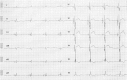

A 32-year-old man with Duchenne muscular dystrophy (DMD) was admitted to the hospital because of worsening dyspnea and general fatigue. He had received medication therapy for cardiomyopathy with heart failure and home mechanical ventilation for respiratory failure. An electrocardiogram on admission showed intermittent third-degree atrioventricular block. Echocardiography showed global mild left ventricular systolic dysfunction with dyssynchrony (ejection fraction: 45%). He underwent implantation of a cardiac resynchronization therapy-defibrillator. His B-type natriuretic peptide level was improved after cardiac resynchronization therapy-defibrillator implantation, and he remains asymptomatic. The incidence of cardiomyopathy increases with age. By adulthood, 100% of patients have cardiac involvement.